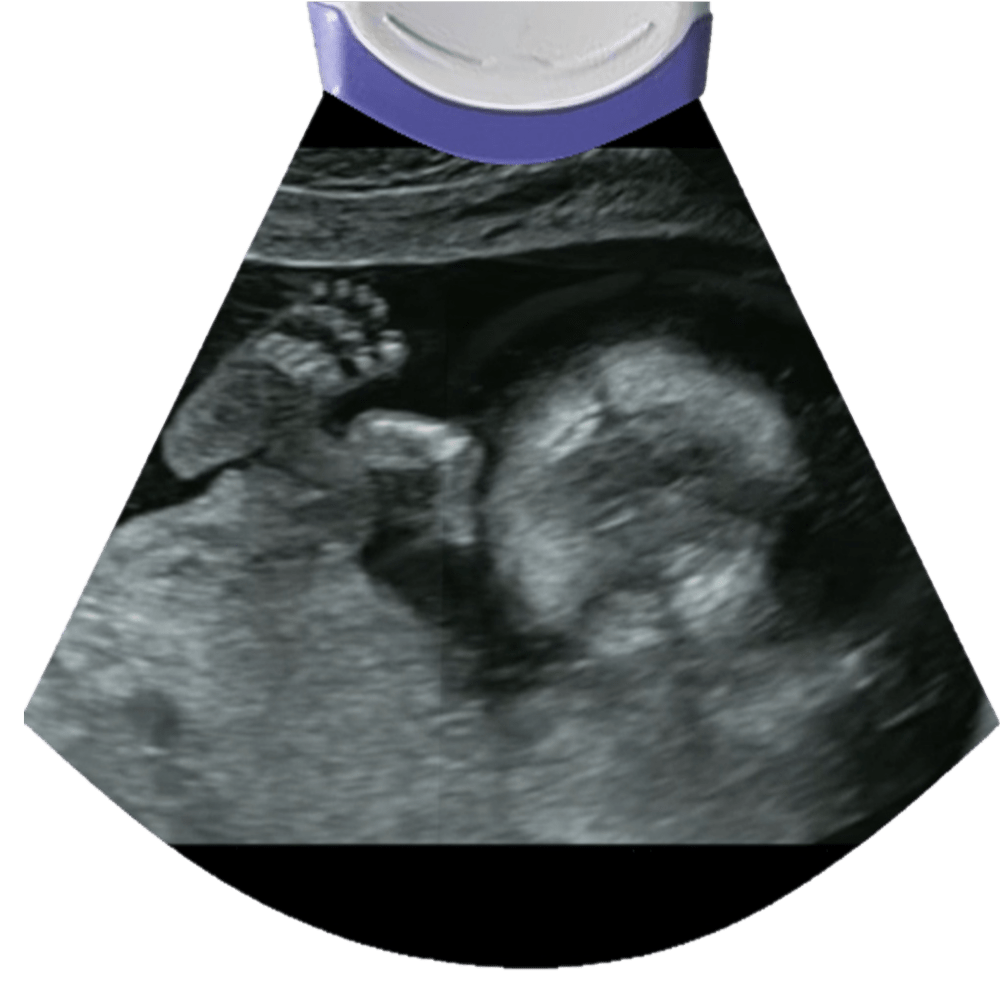

A second trimester sonogram is usually performed between weeks 18-20.

The Scan

Proceed to check the fetus in a head to toe fashion. Begin with the head, you’ll take measurements like the biparietal diameter (BPD), head circumference (HC) and survey the intracranial anatomy like the cerebellum, posterior fossa and lateral ventricle to name a few.

Scan both arms, confirm the presence of bilateral humeri, radius and ulna. Check for asymmetries or size discrepancies that can be related to skeletal dysplasias.

Check the number of fingers.

Make sure there are 5 toes in each foot, look for things like club foot, rocker bottom foot and sandal gap.